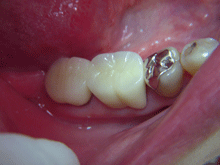

セ ラ ミ ッ ク ク ラ ウ ン

内面には金属を使用し、外面にセラミックを築成するタイプで、従来多くがこの方法で治療されていました。

症 例